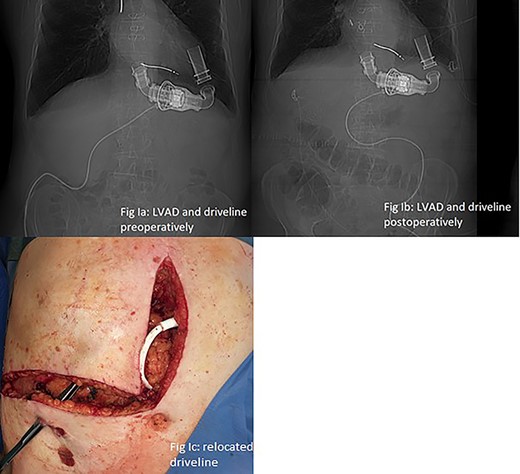

LVAD-driveline was then dissected from scarring tissue, disconnected from its controller for 30 s and repositioned in the left upper quadrant. Circulation was maintained with the use of epinephrine and norepinephrine. Figure 2a and b show preoperative and postoperative driveline positions. Figure 2c shows relocated driveline position and former driveline exit.

(a and b) LVAD and driveline in preoperative and postoperative CT scan scout. (c) Relocated driveline during laparotomy, forceps in former driveline exit.